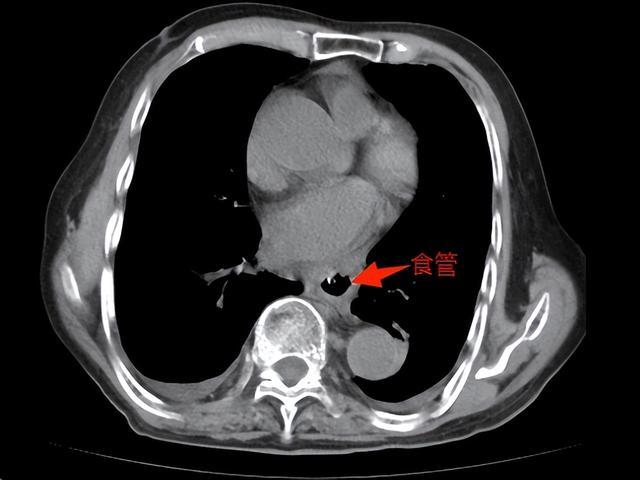

82岁的王爷爷来自湖南岳阳,两三年前开始出现烧心(平躺时尤甚)和进食后呕吐的情况,在当地医院接受护胃、补液等对症治疗,效果甚微。2025年初,老人腹痛、呕吐症状加剧,CT检查发现:他整个胃腔及部分横结肠“顶入”胸腔,形成“胸腔胃”。

▲术前,胃及横结肠“顶入”胸腔